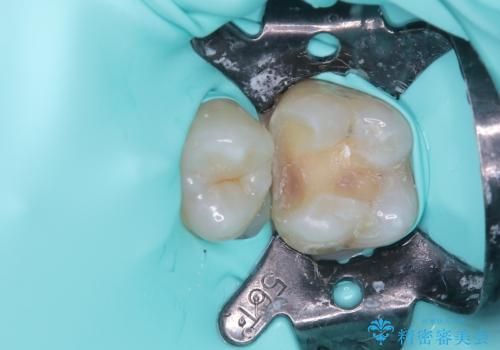

精度の良いインレーを製作するために、シリコーンにて型どりしました。

また確実な接着操作を行うために、インレーを接着する際にはラバーダム防湿を行いました。